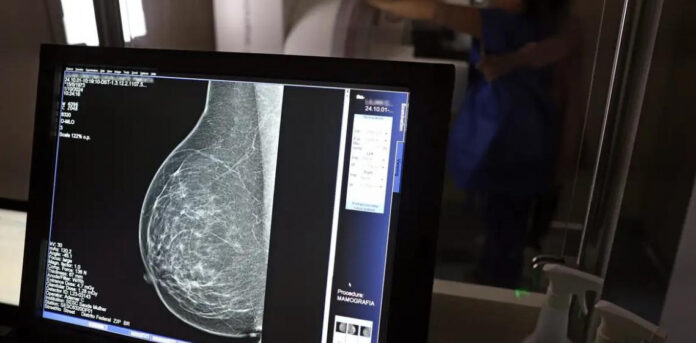

No mês de conscientização sobre o câncer de mama, um relatório destaca a importância de acesso igualitário ao rastreamento e tratamento da doença. Segundo o Atlas da Radiologia no Brasil, do Colégio Brasileiro de Radiologia e Diagnóstico por Imagem (CBR), o acesso aos mamógrafos ainda é um desafio.

O país tem 6.826 equipamentos registrados, sendo 96% em funcionamento. Metade deles está disponível no Sistema Único de Saúde (SUS), responsável por atender 75% da população. Isso equivale a 2,13 mamógrafos por 100 mil habitantes dependentes do SUS.

Na saúde suplementar, que cobre 25% da população, o cenário é mais favorável: 6,54 aparelhos por 100 mil beneficiárias, quase o triplo da rede pública. O Acre exemplifica essa disparidade — são 35,38 mamógrafos por 100 mil habitantes na rede privada, contra 0,84 no SUS.

Há disparidades regionais. Roraima tem a menor proporção (1,53 por 100 mil), seguida do Ceará (2,23) e Pará (2,25). A Paraíba lidera o ranking (4,32), à frente do Distrito Federal (4,26) e do Rio de Janeiro (3,93).

O Brasil tem uma cobertura muito baixa de mamografias: 24%. O ideal recomendado pela Organização Mundial da Saúde é de 70%. Mesmo em lugares como o estado de São Paulo, que tem a maior concentração de mamógrafos do país, a taxa gira em torno de 26%.

Em setembro, o Ministério da Saúde ampliou as diretrizes de rastreamento, recomendando que mulheres entre 40 e 49 anos realizem mamografias, mesmo sem sintomas. De acordo com o Instituto Nacional do Câncer (Imca), mais de 73 mil mulheres recebem o diagnóstico de câncer de mama anualmente no Brasil.

“O que é efetivo na redução da mortalidade é você descobrir o tumor antes de ter sintoma clínico. Quanto menor o tumor, melhor para a gente descobrir o tratamento e maior a chance de cura. E a gente só consegue fazer isso com exames de imagem”, diz Ivie.

Ela explica que no caso de diagnóstico de um câncer de mama com menos de 1 cm, a chance de cura é de 95% em cinco anos, independentemente se ele é do tipo mais agressivo. “E esses tumores só vão ser detectados na mamografia. Essas pessoas que têm que ir fazer mamografia são mulheres saudáveis. Não são mulheres doentes”, acrescenta.